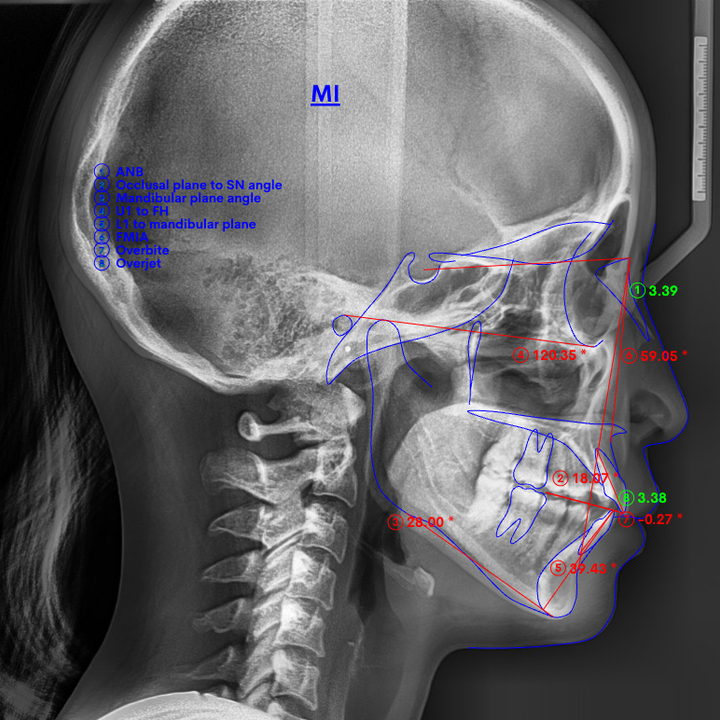

精密検査